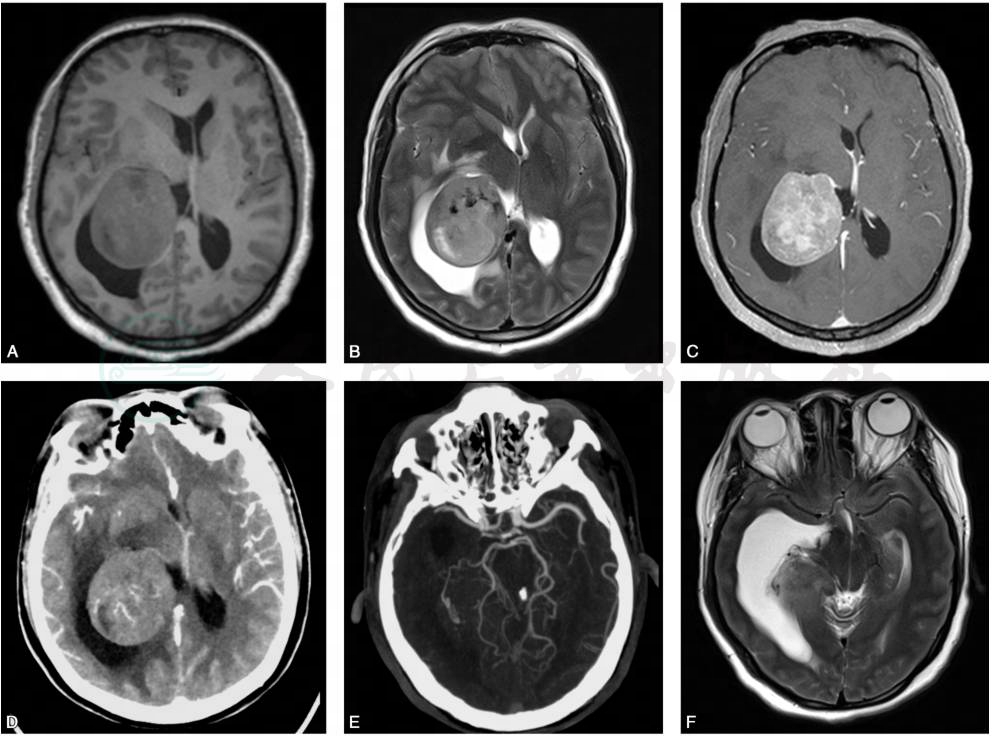

图2脑室内脑膜瘤的影像表现

A.T1加权MRI平扫见肿瘤位于侧脑室三角区,质地均匀,信号与周围脑组织相当,室间孔堵塞;B.T2加权MRI平扫见肿瘤信号较不均匀,肿瘤周围脑组织受压水肿;C.T1加权MRI增强扫描示肿瘤强化明显,与周围结构界限清晰;D.CT增强检查示肿瘤中等强化;E.CTA检查示肿瘤供血动脉增粗迂曲;F.T2加权MRI平扫见侧脑室颞角积水